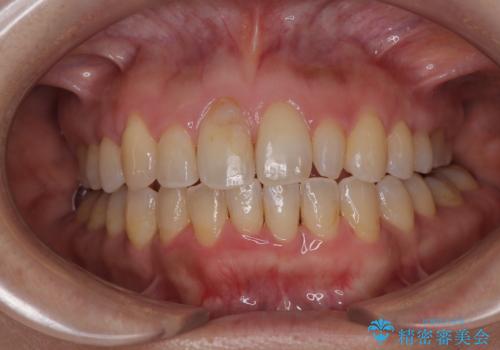

銀歯を白くしたい 一緒に矯正治療も行ない美しい口腔内に